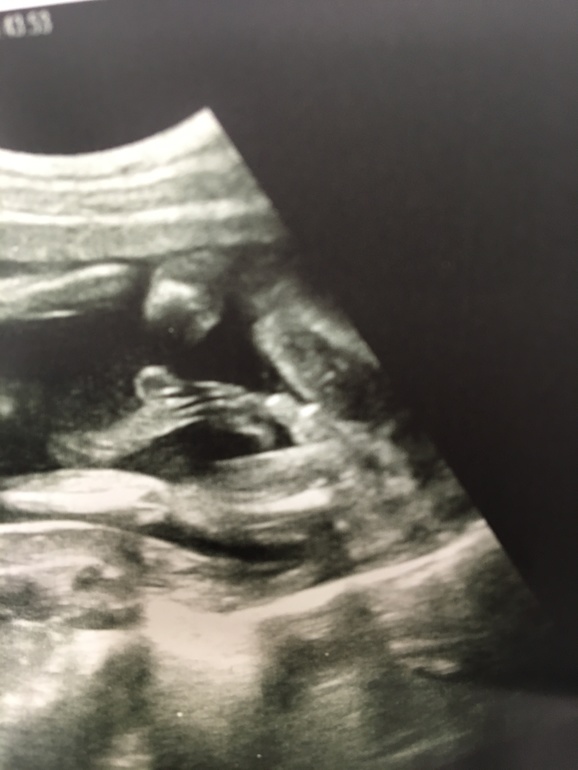

Время закрашивать кружок👉🏻👦🏻!

Ну,не умеем мы девочек делать!У моих родителей это 4ый внук и ни одной внучки🤷🏻♀️!Наверное надо было цветы под подушку положить,головой на юг лечь,на пуховой перине зачинать малыша...Папа наш счастлив!Я тоже не расстроилась,но никогда не думала,что буду мамой 2 сыновей!...Берегитесь снохи!Тещей будет кто-то другой)!